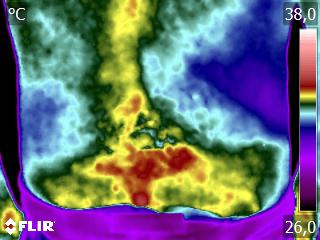

Como no caso do termograma abaixo de um paciente, do sexo masculino, 51 anos, sem comorbidade e que apresentou dor em região lombar. Foi realizado uma Análise Termofuncional e detectado alterações térmicas que corroboraram o relato de dor.

Estas informações permitiram a imediata decisão para a mudança do tratamento e direcionamento da terapia para a diminuição da dor.

Tudo isto em apenas uma sessão.